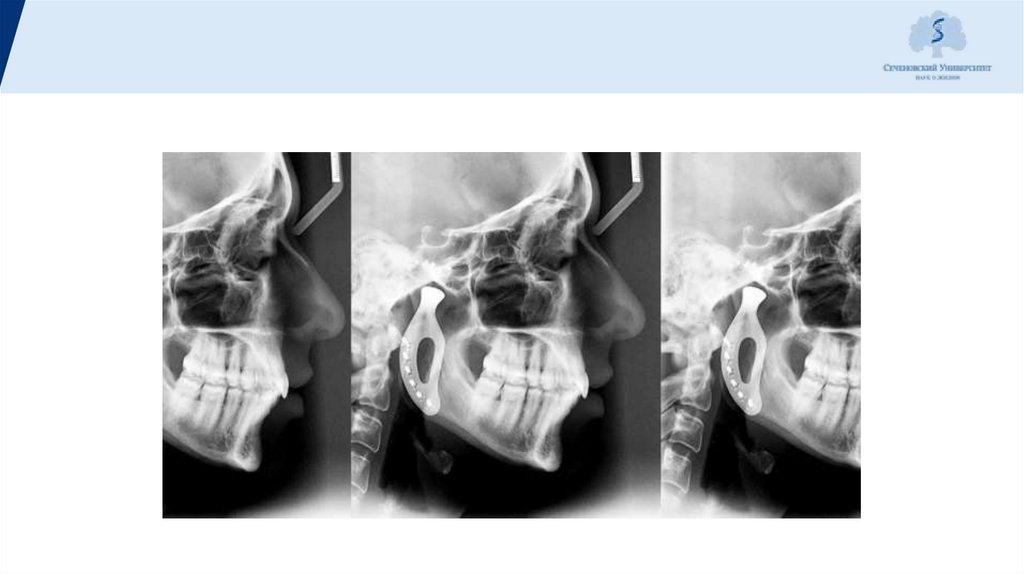

Tomograms of the right

and left TMJ. Diagnosis:

right-sided

neuromuscular

dysfunctional TMJ

syndrome